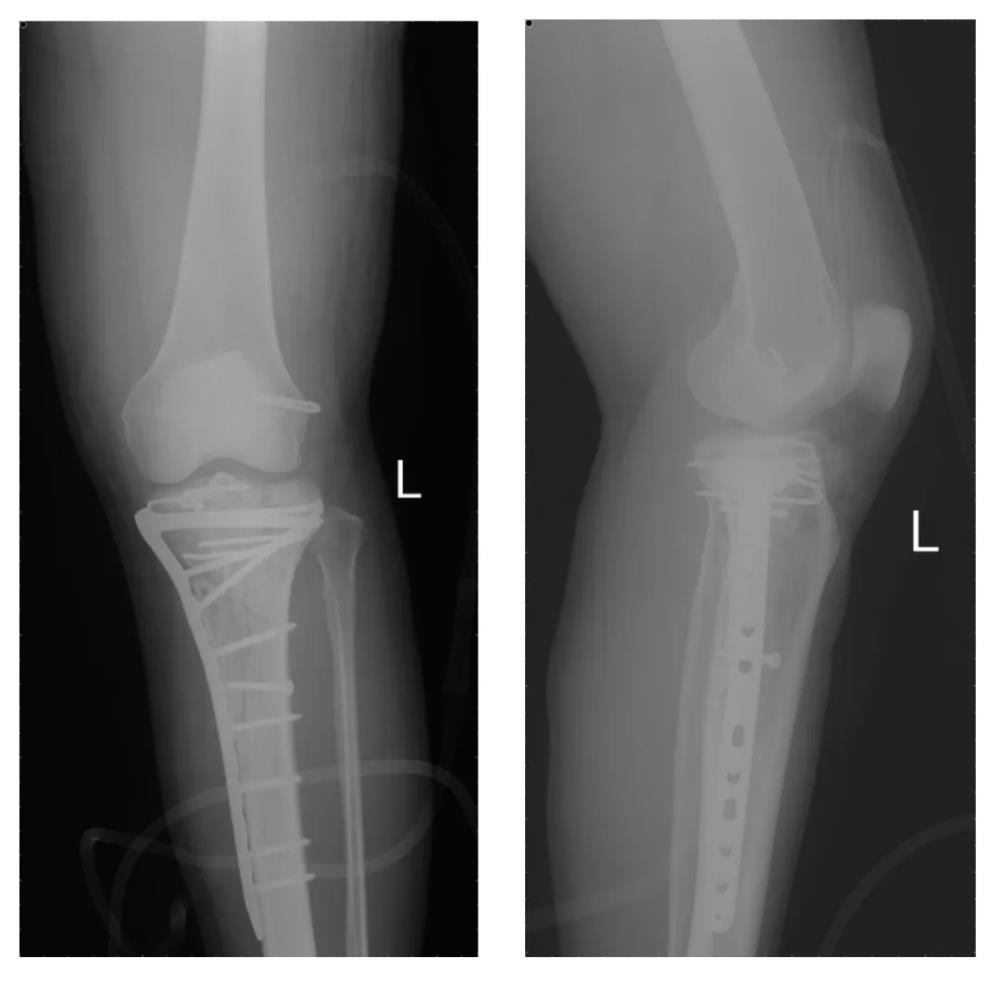

当严重的粉碎性关节骨折遇上数字化医疗,会发生怎样的化学反应?近日,玉林市中西医结合骨科医院膝关节病与运动损伤科联合医学3D打印临床中心,成功实施了一例高难度左胫骨平台粉碎性骨折修复手术。通过1:1的骨骼复刻模型,医生团队在术前就对骨折分离移位“了如指掌”,为患者带来了真正的个性化、精准化治疗。

56岁的樊女士怎么也没想到,一次意外竟让她的左膝遭遇了如此严重的创伤。入院时影像检查结果触目惊心:左胫骨上段及胫骨平台粉碎性骨折,伴有股胫关节失稳。胫骨平台是膝关节重要的负重结构,粉碎性骨折后关节面平整度直接决定术后膝关节功能恢复情况,若复位不佳、固定不稳,极易引发创伤性关节炎、关节僵硬、行走疼痛、跛行等终身后遗症,严重影响中老年患者生活质量。

精准诊断:肉眼可见,左胫骨上段及胫骨平台呈粉碎性骨性结构中断,骨块分离情况严重;

关节评估:关节面粉碎骨折,关节面塌陷,外侧关节面向外上脱位,内侧关节面出现明显倾斜。

术后,樊女士的骨折端得到了完美复位,关节面的塌陷得到了恢复,为后期康复奠定了坚实的基础。